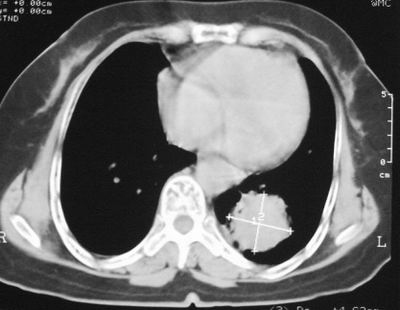

患者,女,64岁,4年前左腮腺"多形性"腺瘤手术治疗史.现复查胸部ct见左下肺块状影,该影与原左腮腺手术是否有联系?

本次复查胸部ct

左下肺软组织块影,有分叶、毛刺、空泡及胸膜牵拉征,左下肺周围性肺癌。

左肺下叶周围型肺癌,支持!(软组织肿块+分叶+毛刺+空泡+胸膜凹陷征)

左下肺软组织密度影,可见分叶,边缘可见毛刺征,胸膜增厚,强烈要求左下肺周围型肺癌

左下肺后基底段实性肿块,周围有毛刺,病变周围有肺气肿,与降主动脉间有条带状影相连,病灶4年前查体发现,纵隔内未见肿大淋巴结。考虑.肺隔离症,建议增强扫描与周围型肺癌鉴别。